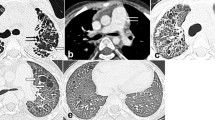

HRCT protocol and image evaluation

A detailed description of the HRCT protocol, HRCT pattern definitions and HRCT scoring method can be found in the online repository. Two thoracic radiologists of 9 and 10 years’ experience scored HRCTs for each patient on the total disease extent, the extent of four interstitial patterns (ground glass opacification, reticulation, honeycombing and consolidation) and emphysema, at six levels. A score of the severity of traction bronchiectasis (0–3) was also assigned. At the end of scoring, each patient had a total disease extent score, for total extent scores for each of the four interstitial patterns, a total emphysema extent score and a total traction bronchiectasis score (examples are shown in Figs. 1, 2 and 3).